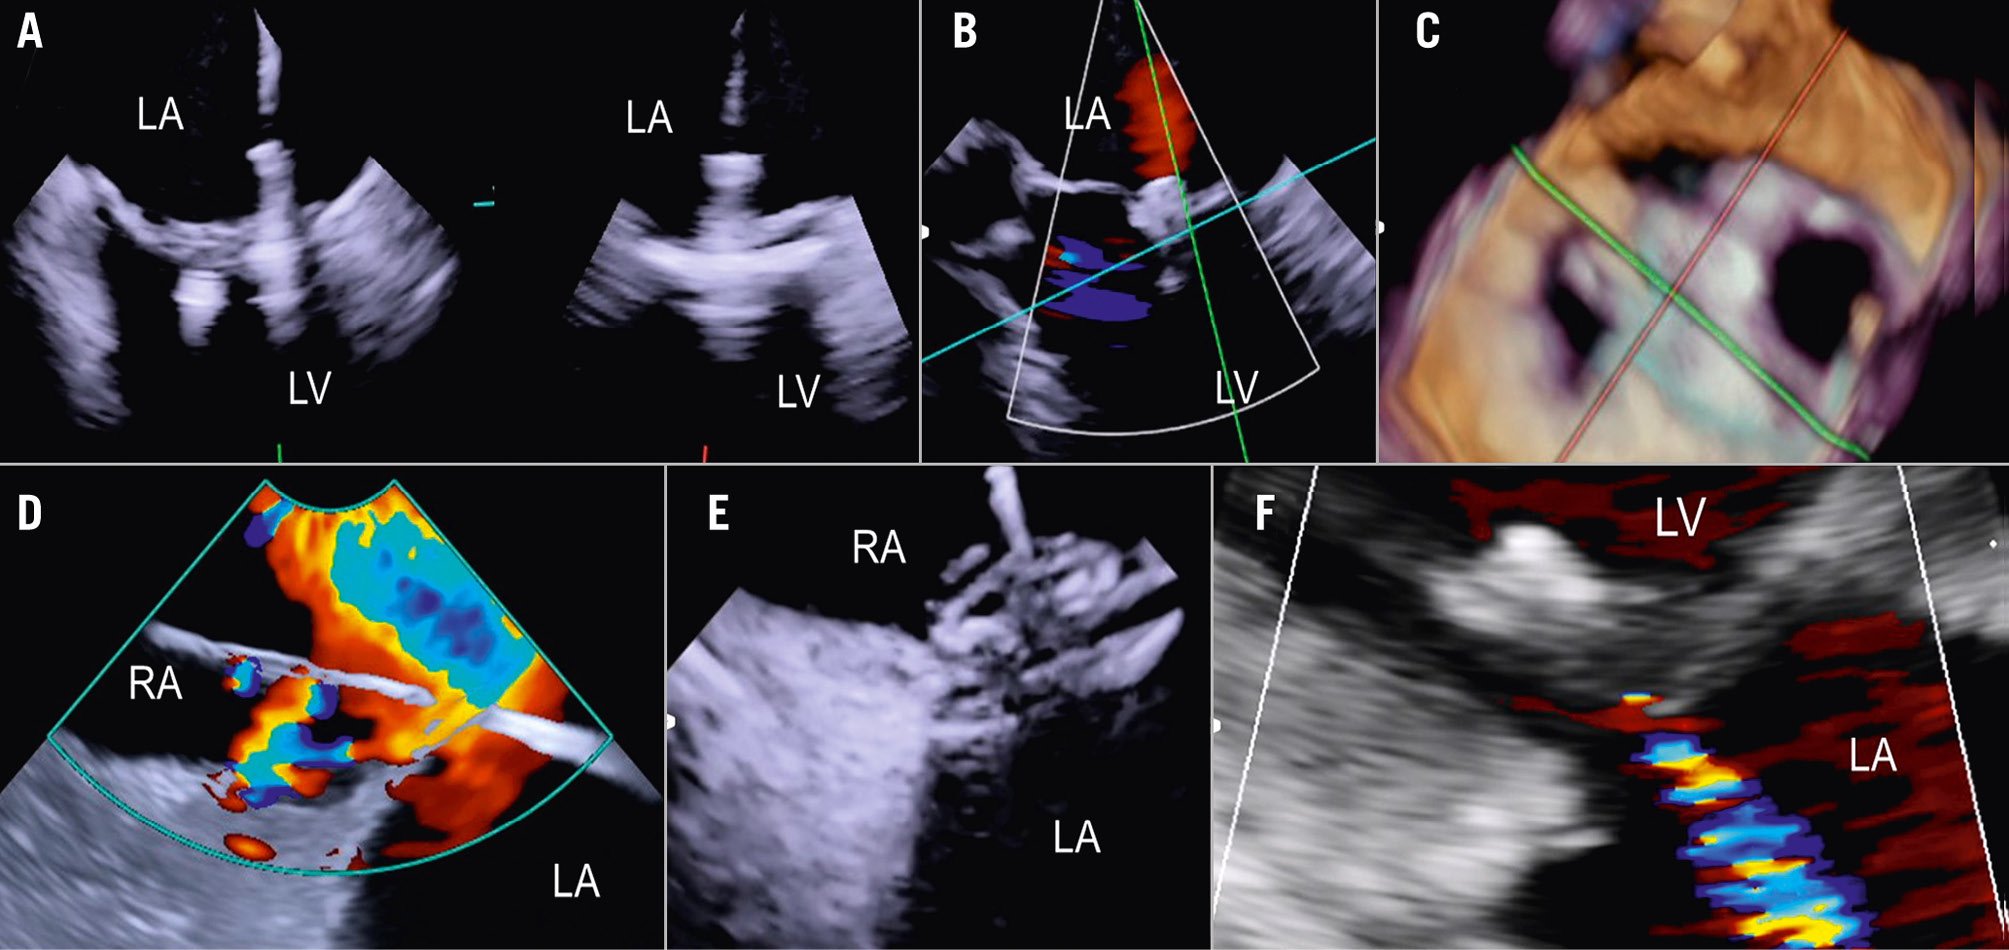

Imaging the MV with ICE implies crossing the interatrial septum and positioning the imaging catheter in the left atrium, a step that can be technically challenging. The TSP is performed using simultaneous biplane imaging with the ICE catheter positioned in the middle of the right atrium and retroflexed towards the septum (Figure 7A). A preshaped stiff wire is carefully positioned into the upper left pulmonary vein under fluoroscopic and ICE guidance (Figure 7B). Predilatation of the septum is required to facilitate the advancement of the ICE catheter into the LA while tracking the trajectory of the wire (Figure 7B). This can be done either by advancing and retracting the TEER-guiding catheter or through preparatory balloon septostomy using a 12-14 mm over-the-wire percutaneous transluminal angioplasty balloon. Once the ICE catheter has been placed successfully into the left atrium, it is followed by the guiding sheath, and the implant itself is then advanced towards the diseased MV (Figure 7C). While the ICE catheter usually follows the curve of the delivery system, a position below it (Figure 7D) or the use of the right and left deflexion knob minimises shadowing artefacts and avoids direct interaction with the TEER device or any other catheter used for the intervention. The key advantage of RT 3D catheters is the ability to produce MPR that facilitates simultaneous optimisation of the trajectory and orientation in several planes and on the 3D view from the atrium (Figure 8, Figure 9A-Figure 9B-Figure 9C, Moving image 9-Moving image 10-Moving image 11). At the end of the procedure, closure of the interatrial septum should be considered (Figure 9D), since the defect is usually larger than after conventional TEER due to the manipulation of two catheters through the same access. Closure can be easily guided with the ICE catheter back to the right atrium (Figure 9E). Mini-TOE or a paediatric probe (without 3D capabilities), as well as transthoracic echocardiography26 are additional confirmatory imaging modalities that can be used in combination with ICE (Figure 9F).

Figure 9. ICE-guided mitral valve transcatheter edge-to-edge repair. A) Implantation of two clips and leaflet capture under ICE visualisation; (B) final result after implantation of two clips for correction of a posterior flail; (C) 3D ICE view of the MV after implantation of two clips; (D) large iatrogenic ASD visualised from the right atrium and crossed by a wire; (E) ASD closure using a 14 mm Amplatzer Septal Occluder under ICE guidance; (F) final result with mild residual MR as shown by transthoracic echocardiography at discharge. 3D: three-dimensional; ASD: atrial septal defect; ICE: intracardiac echocardiography; LA: left atrium; LV: left ventricle; MR: mitral regurgitation; MV: mitral valve; RA: right atrium; RV: right ventricle